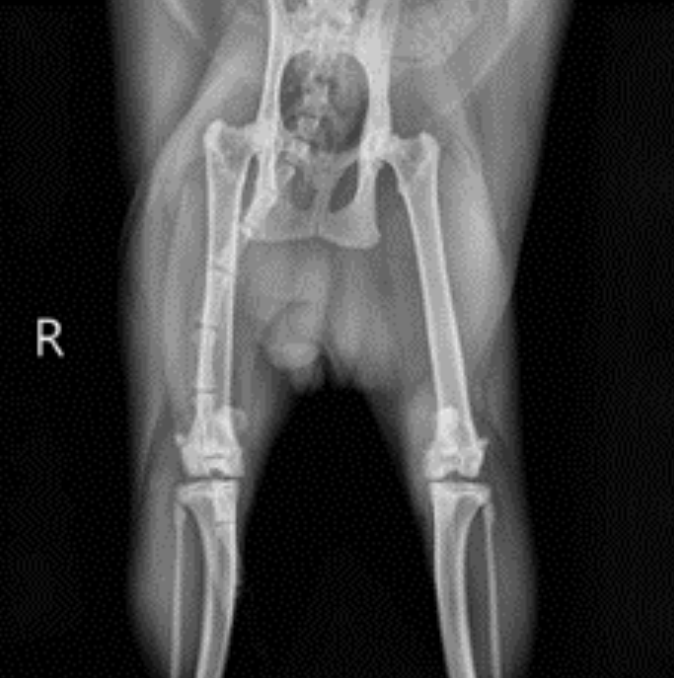

방사선 검사 : 후지 방사선 상 복배상(VD view)에서는 양측 슬개골이 활차구 내 위치하지 않고 내측으로 변위되어 있는 모습을 확인할 수 있었습니다. 또한 양쪽 무릎관절 전반에 걸쳐 골극(Osteophyte) 형성, 관절 내 삼출액 등 퇴행성 관절염 소견이 확인되었습니다. ▼